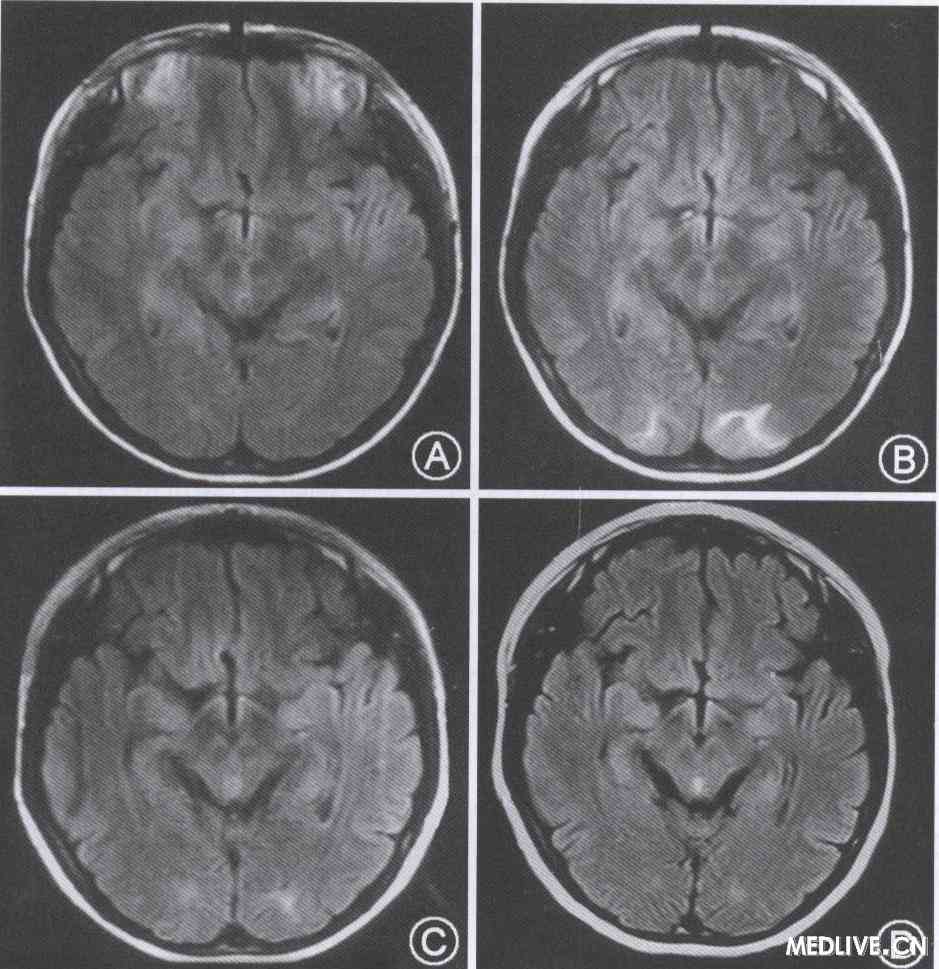

图1患者4次头颅MRI(FLAIR像)。A:首次MRI检查未见异常(病程第42天);B:第2次MRI检查示双侧枕叶病变(病程第52天,癫痫发作后第5天);C:第3次MRI检查显示病灶缩小(病程第63天);D:第4次MRI显示病变完全消失(病程第81天)

眼底照相:左眼视神经萎缩,右眼部分视神经萎缩。红绿色盲。测视力双眼0. 06。乳酸丙酮酸试验:最小运动量试验轻度异常;前臂半缺血运动试验大致正常。2010年3月29日头颅MRI未见异常(图1);4月5日复查显示双枕叶片状长T.、T2信号,以左侧为著;4月18日复查双枕叶可见长T1、T2信号,以左侧为著,病变较前缩小;5月5日MRI病变消失。肌肉活体组织检查大致正常。基因检测:mtDNA G11778A突变,mtDNA 3243位点未见突变。

本例患者通过基因检测确诊为LHON。患者13岁发病,病程初期双眼几乎同时出现无痛性中心视野视力下降。随后发现红绿色盲,眼底检查示双侧视神经萎缩,与LHON的临床特点相符。该病的早期很多病例被误诊为“双眼视神经炎”。患者在起病47 d出现线粒体脑肌病伴高乳酸血症和卒中样发作综合征( MELAS)的最常见症状:头痛和癫痫发作。MELAS患者的卒中样发作常累及枕叶和顶叶,临床表现为局灶性力弱、言语障碍、偏头痛或癫痫发作,伴随相应的脑实质损害,典型表现为灰白质均受累,类似脑梗死。本例患者头颅MRI表现与患者的癫痫发作密切相关,病灶累及皮质一皮质下结构,MRI显示病灶逐渐缩小,41 d后完全消失,类似MELAS病灶的演变过程[4]。